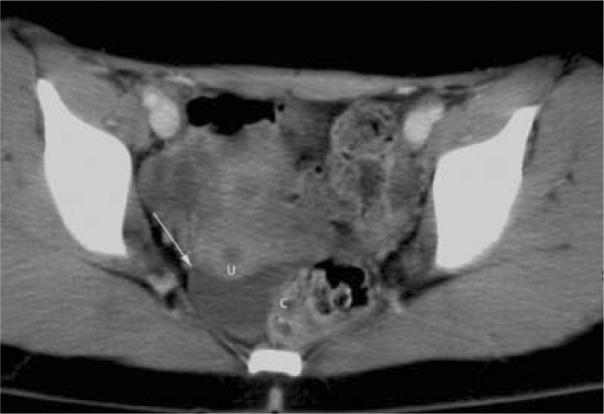

Concave Margin Sign on CT as an Indication of Ascites.

Ascites is found in a variety of conditions, both acute and chronic, and computed tomography (CT) is usually successful in detecting its presence. We reviewed the CT images from a three-month window of patients in order to evaluate the prevalence and utility of a new radiographic sign for diagnosing ascites.